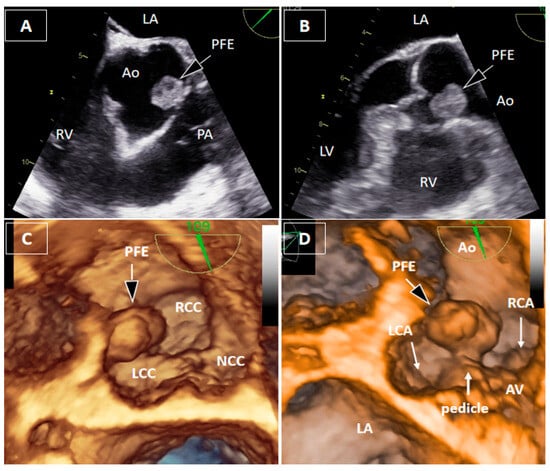

Papillary Fibroelastoma of the Aortic Root Causing Intermittent Coronary Ostial Obstruction: The Diagnostic Power of 3D Transesophageal Echocardiography

Bečić, T.; Perković-Avelini, R.; Fabijanić, D. Papillary Fibroelastoma of the Aortic Root Causing Intermittent Coronary Ostial Obstruction: The Diagnostic Power of 3D Transesophageal Echocardiography. Diagnostics 2026, 16, 168. https://doi.org/10.3390/diagnostics16010168